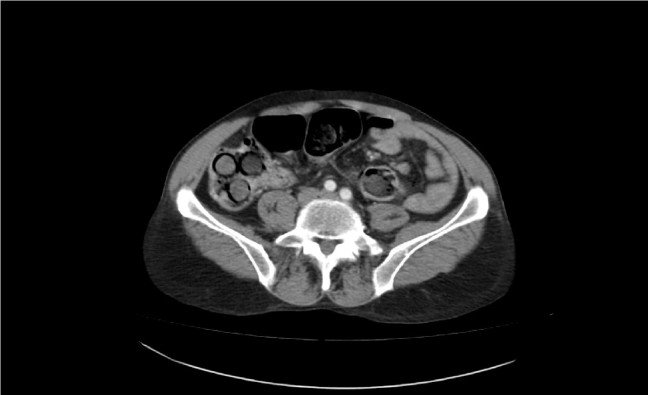

İran uyruklu S.R'nin midesinde tespit edilen 49 paketteki 775 gram saf eroin endoskopiyle alındı.